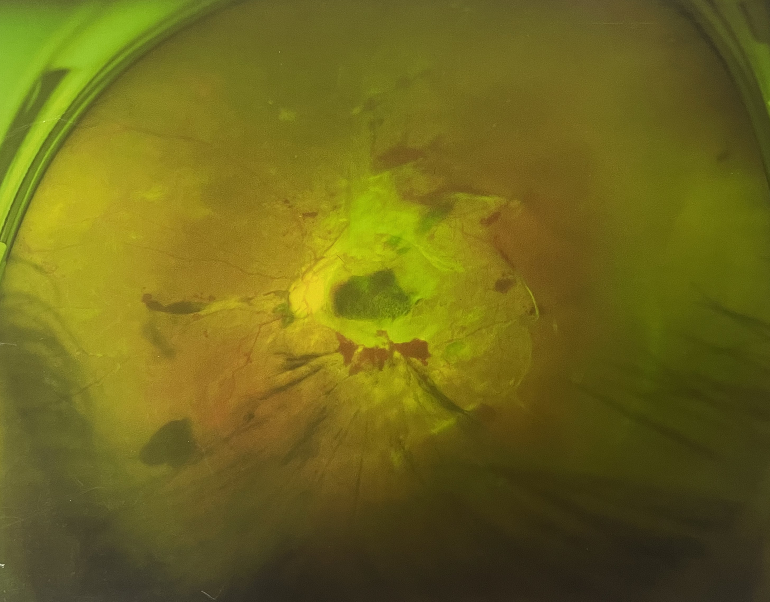

4個(gè)月前的左眼

左眼發(fā)展到糖尿病視網(wǎng)膜病變VI期

由于王女士的左眼沒(méi)有聽(tīng)從醫(yī)生盡快做手術(shù)的建議,一直耽誤,從4月前的0.4視力逐漸下降到僅剩眼前手動(dòng),導(dǎo)致左眼發(fā)展到糖尿病視網(wǎng)膜病變VI期(屬于6期糖網(wǎng)中的晚期),已經(jīng)產(chǎn)生大量新生血管+纖維增值+廣泛牽拉性視網(wǎng)膜脫離,由于耽誤了病情,且病情發(fā)展異常迅速,導(dǎo)致目前左眼連保住眼球都很困難。

“而如果4月余前,左眼及時(shí)手術(shù)(當(dāng)時(shí)左眼病情比右眼輕,增殖膜還未累及黃斑),左眼將恢復(fù)的比右眼還好,甚至可以恢復(fù)到0.8或1.0,而現(xiàn)在連保住眼球的機(jī)會(huì)都很渺茫”,張小虎醫(yī)生表示實(shí)在可惜。